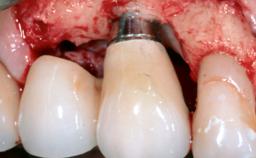

Surgical Management of Peri-Implantitis: Removal of Implant Due to Recurrent Infection Using an Implant-Retrieval Tool

Despite anti-infective surgical treatment, some patients may experience recurrent infection and progressive bone loss requiring additional treatment. This case describes a conservative approach using an implant retrieval tool without the need for excessive bone removal or use of a trephine.

A 65-year-old female patient was referred to the periodontist for assessment and management of infection associated with an implant at site 12. The general dentist had noted suppuration on probing during examination.